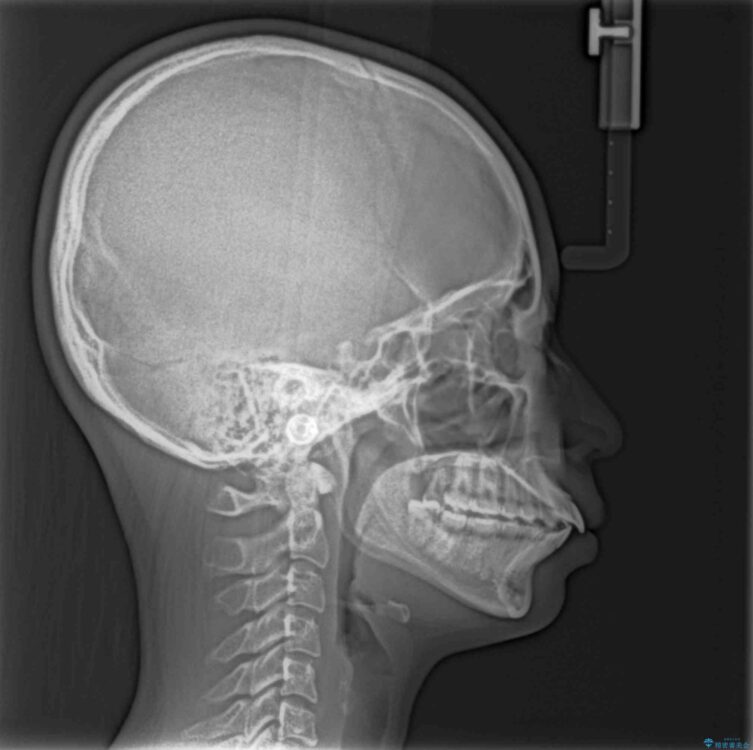

治療前

• 【モニター】口が閉じられない ワイヤー装置での抜歯矯正 治療前画像

上下の前歯が突出しており、口が閉じにくいとのことで来院された患者様です。

上下前歯が著しく前突している状態であったので、上下左右の第1小臼歯4本を抜歯し、ワイヤー装置にて矯正治療を行うこととしました。

舌の突出癖により、前突になったと考えられたため、舌のトレーニングをしっかりと行うよう指導しました。